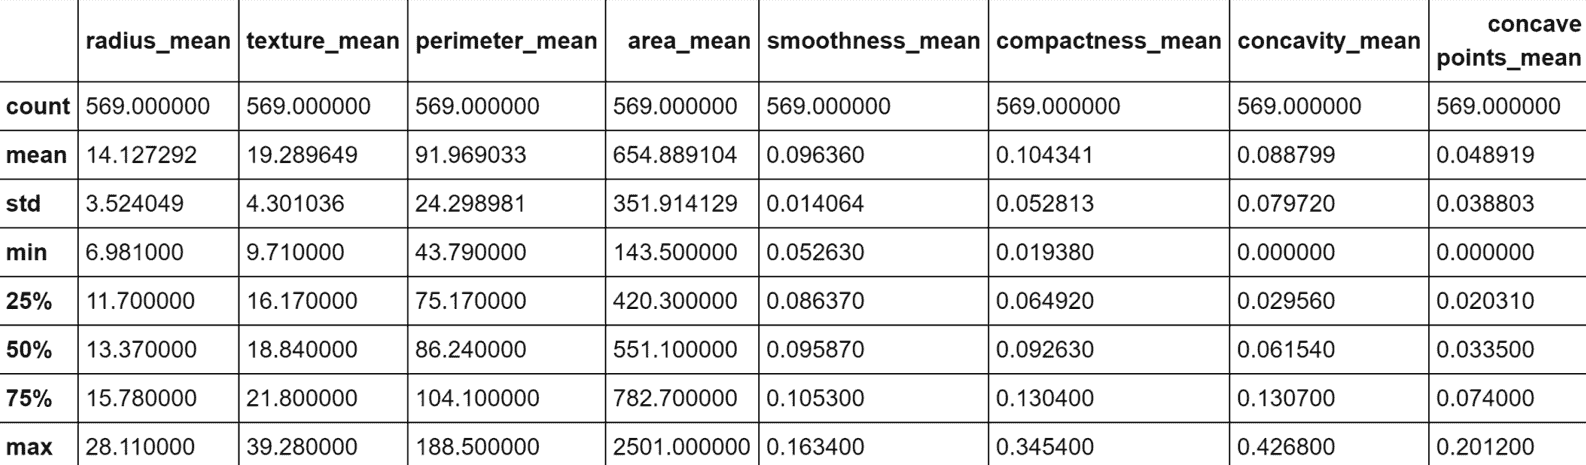

生成的绘图显示在以下屏幕截图中:

乳腺癌威斯康星州数据集的二维 t-SNE 图

该图是高度非线性的(别忘了这是从ℜ^30到ℜ^2的投影),恶性样本中的一半在半平面y < 0中。 不幸的是,在该区域中也有适度的良性样本,因此我们不期望使用K = 2进行完美分离(在这种情况下,很难理解真实的几何形状,但是 t- SNE 保证二维分布的 Kullback-Leibler 散度与原始高维散度最小。 现在,我们以K = 2进行初始聚类。 我们将使用n_clusters=2和max_iter=1000创建KMeans scikit-learn 类的实例(random_state始终设置为等于1000)。